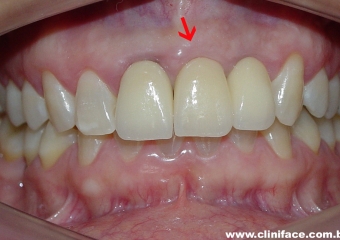

Protese fixa em porcelana no elemento 21

Sorriso final do caso terminado em agosto de 2009